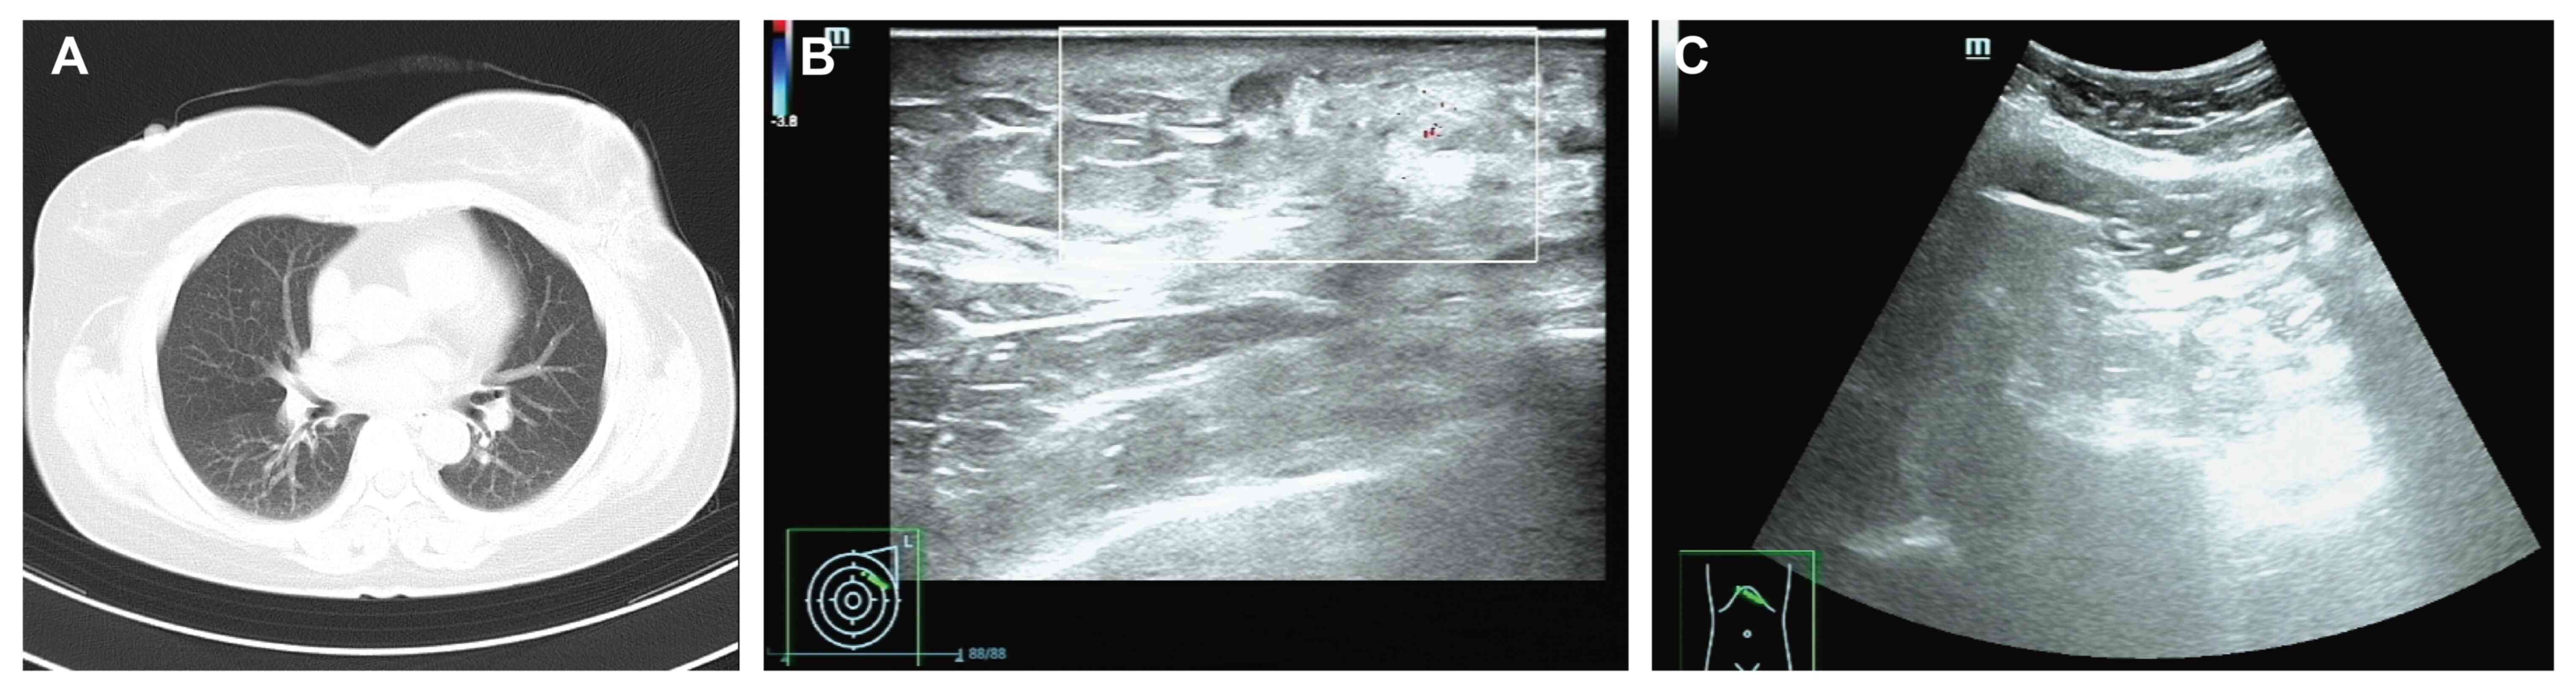

Follow-up evaluations, including chest CT, breast and abdominal ultrasonography, and serum tumor marker assessments, have revealed no evidence of recurrence or metastasis as of May 2025. The most recent tumor marker levels were within the normal ranges as follows: CEA, 3.05 ng/ml (reference value, <4.7 ng/ml); and CA15-3, 19.6 U/ml (reference value, <26.2 U/ml). Radiological follow-up imaging in May 2025 also revealed no abnormal findings: Chest CT revealed no evidence of pulmonary or mediastinal metastasis (Fig. 4A), breast ultrasonography demonstrated postoperative changes in the left breast without signs of local recurrence (Fig. 4B) and abdominal ultrasonography was unremarkable, with no hepatic or peritoneal lesions identified (Fig. 4C). Furthermore, based on the 2024 CSCO Guidelines for Breast Cancer, the patient was recommended to continue AI-based endocrine therapy for 5 years. In addition, a structured follow-up surveillance plan was established, consisting of breast ultrasound every 3 months, and breast MRI and tumor marker evaluations every 6 months. This surveillance strategy aims to enable early detection of locoregional recurrence or distant metastasis, particularly given the unusual site of adipose tissue metastasis observed in the present case. Regular imaging and laboratory assessments are crucial for timely intervention and to improve long-term outcomes in patients with hormone receptor-positive breast cancer (7).

Radiological follow-up imaging of the

patient. (A) Chest computed tomography showing no evidence of

pulmonary or mediastinal metastasis. (B) Breast ultrasonography

revealing postoperative changes in the left breast, with no signs

of local recurrence. (C) Abdominal ultrasonography demonstrating no

hepatic or peritoneal abnormalities.

Figure 4.

Radiological follow-up imaging of the patient. (A) Chest computed tomography showing no evidence of pulmonary or mediastinal metastasis. (B) Breast ultrasonography revealing postoperative changes in the left breast, with no signs of local recurrence. (C) Abdominal ultrasonography demonstrating no hepatic or peritoneal abnormalities.